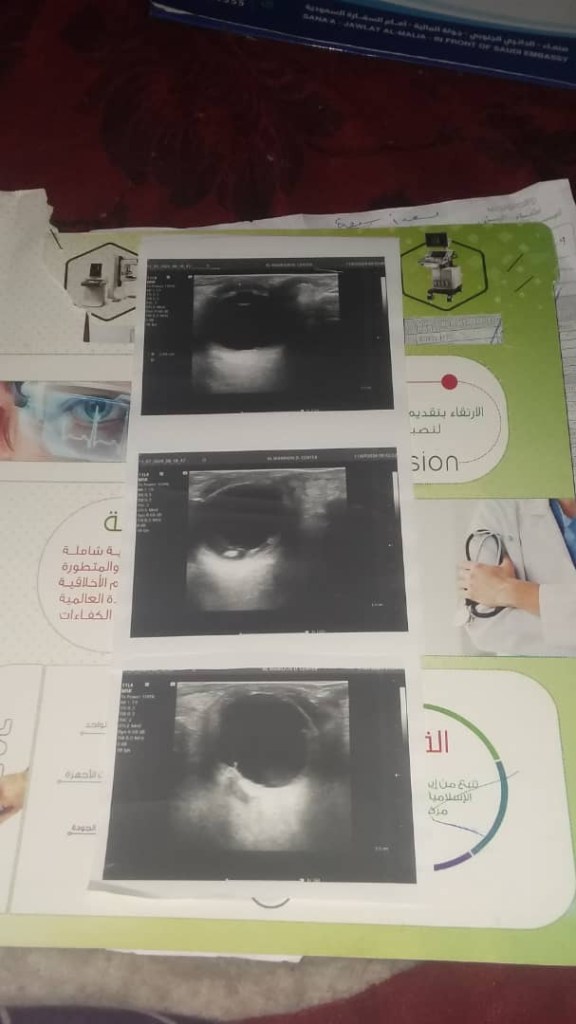

يعاني من فشل كلوي

كما يعاني ضعف في النظر. بحسب التقارير المرفقة